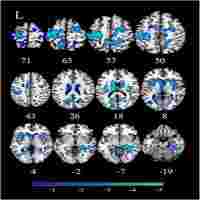

| Description | Journal: Human brain mapping Resting‐state fMRI (RS‐fMRI) has become a useful tool to investigate the connectivity structure of mental health disorders. In the case of major depressive disorder (MDD), recent studies regarding the RS‐fMRI have found abnormal connectivity in several regions of the brain, particularly in the default mode network (DMN). Thus, the relevance of the DMN to self‐referential thoughts and ruminations has made the use of the resting‐state approach particularly important for MDD. The majority of such research has relied on the grand averaged functional connectivity measures based on the temporal correlations between the BOLD time series of various brain regions. We, in our study, investigated the variations in the functional connectivity over time at global and local level using RS‐fMRI BOLD time series of 27 MDD patients and 27 healthy control subjects. We found that global synchronization and temporal stability were significantly increased in the MDD patients. Furthermore, the participants with MDD showed significantly increased overall average (static) functional connectivity (sFC) but decreased variability of functional connectivity (vFC) within specific networks. Static FC increased to predominance among the regions pertaining to the default mode network (DMN), while the decreased variability of FC was observed in the connections between the DMN and the frontoparietal network. Hum Brain Mapp 37:2918–2930, 2016. © 2016 Wiley Periodicals, Inc. |